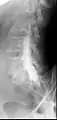

Conventional myelography in oblique projection. You can see the individual nerve root sheaths.

Computed tomography after conventional myelography. The overlap-free representation often allows a more secure assessment. The high density of contrast material may be troublesome in case of insufficient mixing prior to CT.